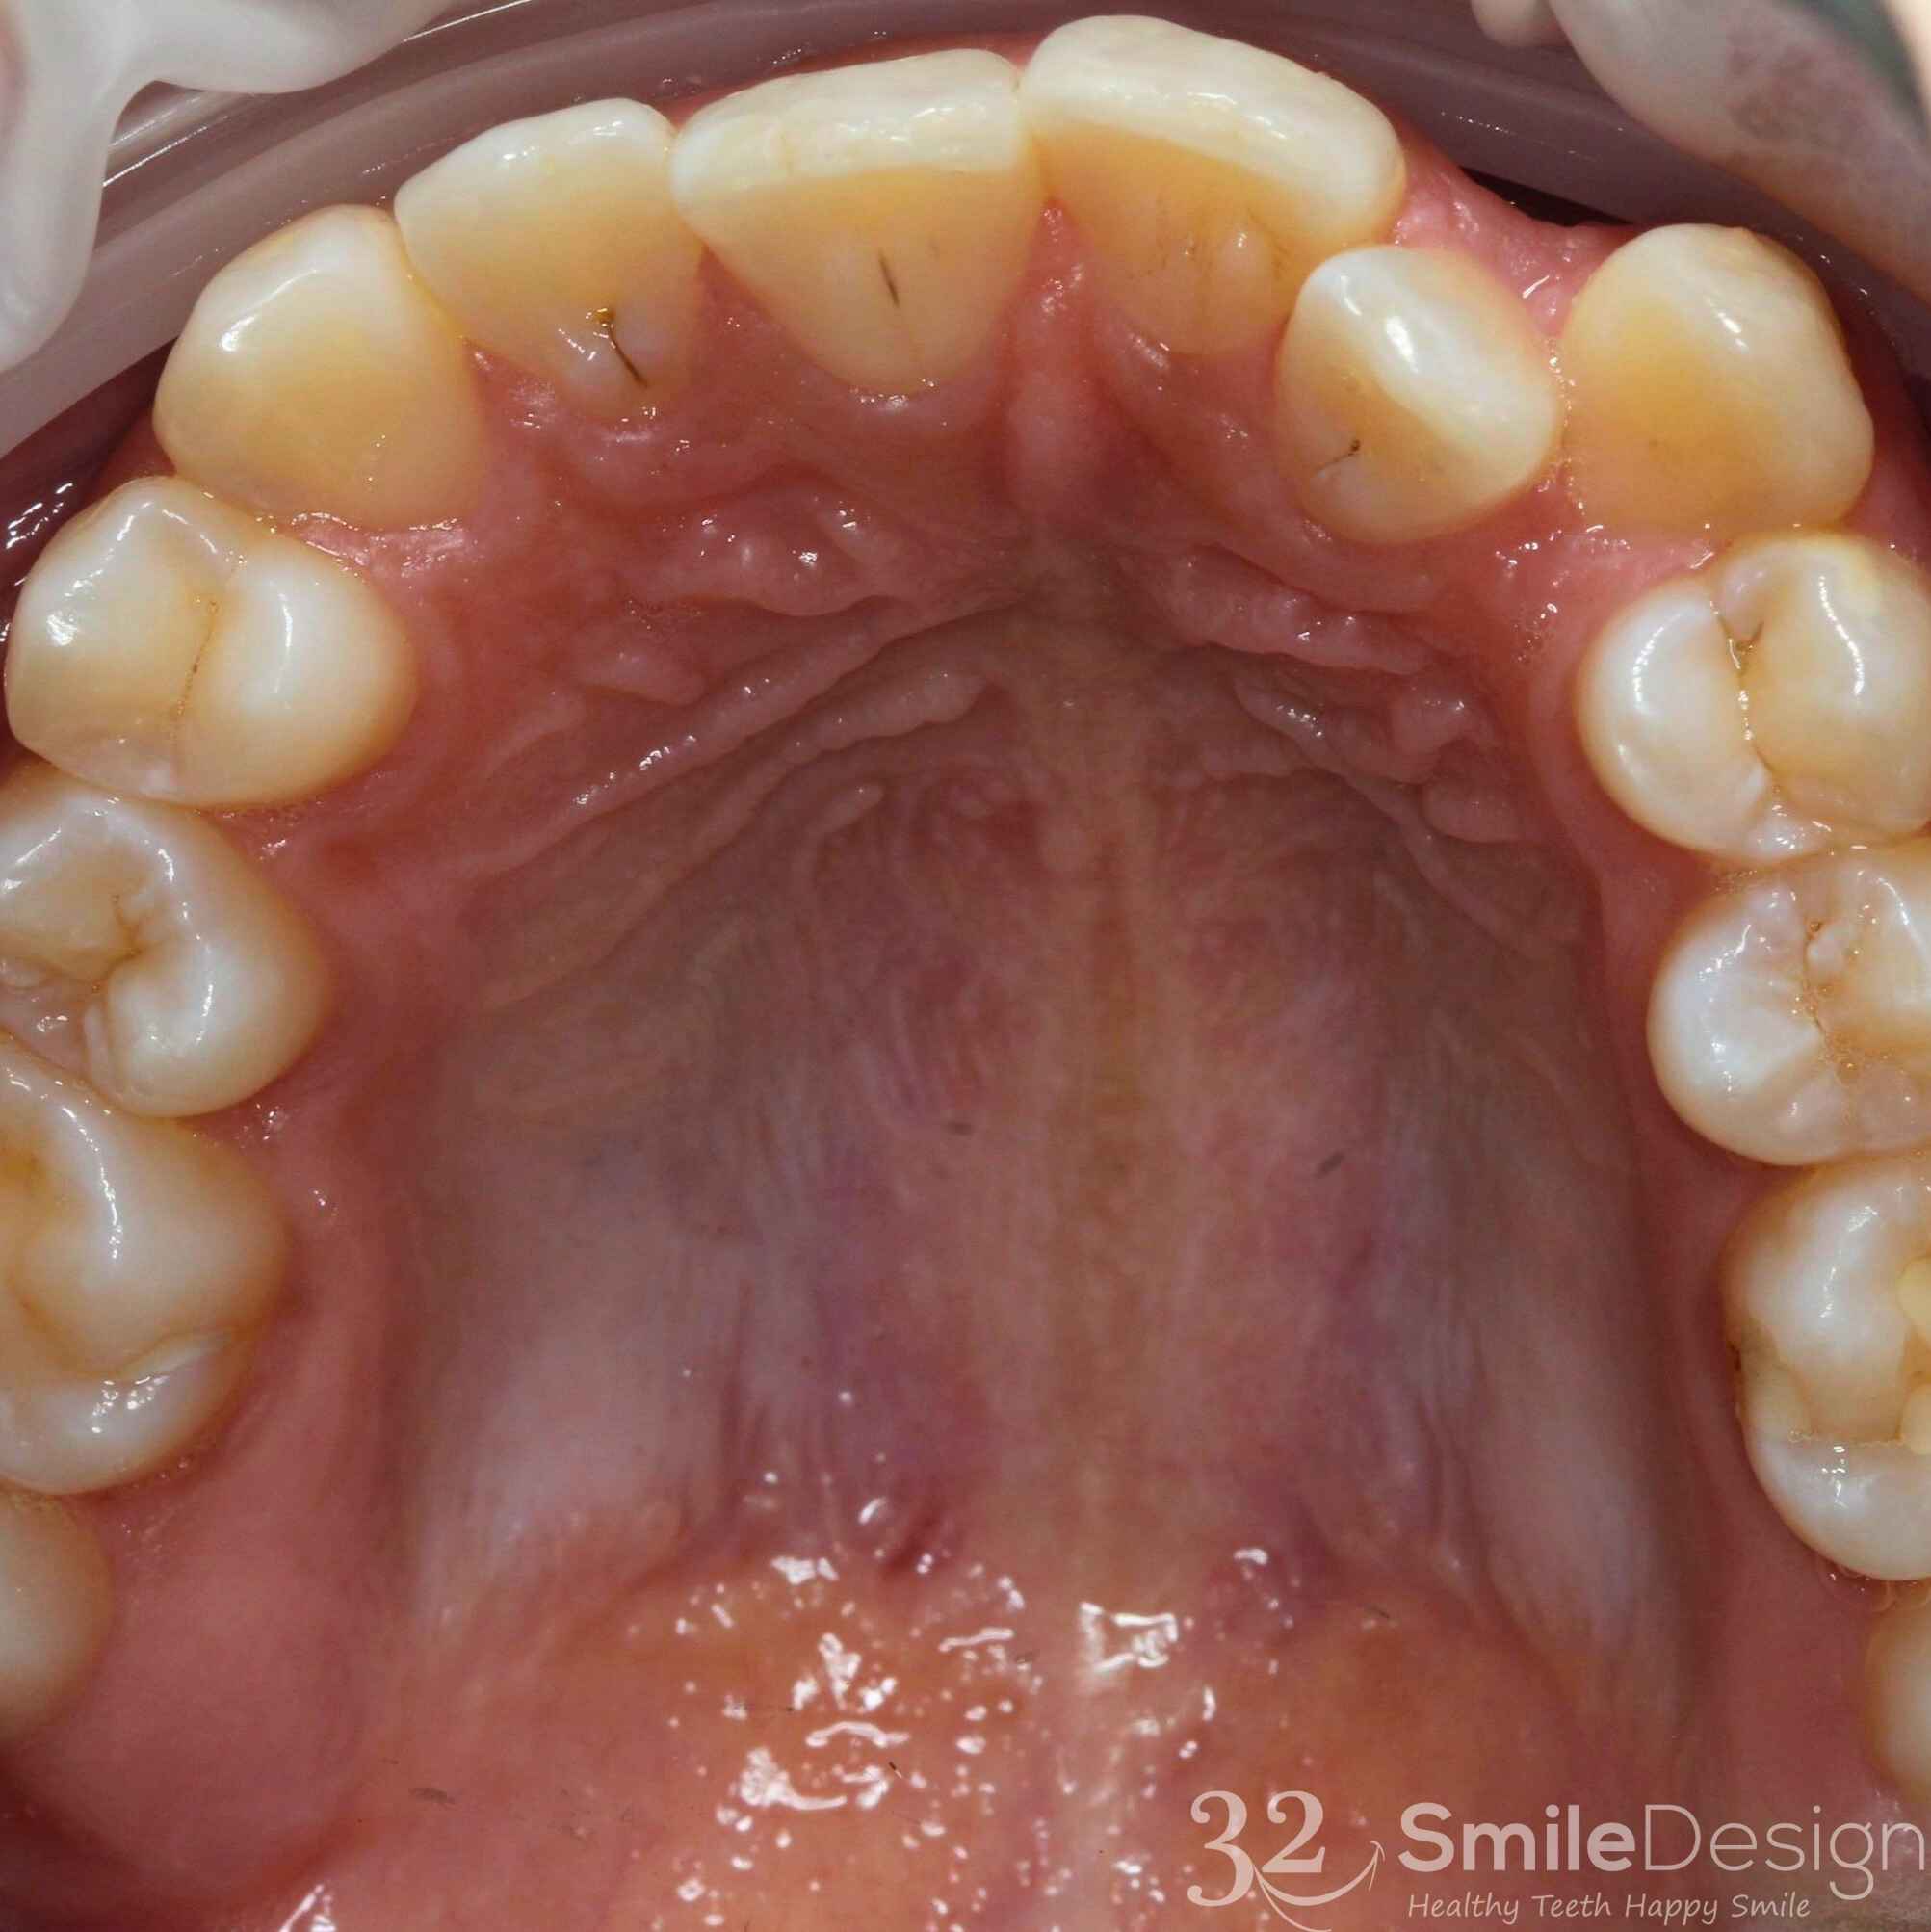

Lower Jaw - Before & After

Upper Jaw - Before & After

Lower Jaw - Before & After

Upper Jaw - Before & After

Lower Jaw - Before & After

Upper Jaw - Before & After

Lower Jaw - Before & After

Upper Jaw - Before & After

Lower Jaw - Before & After

Upper Jaw - Before & After

Lower Jaw - Before & After

Upper Jaw - Before & After

Upper Jaw - Before & After

Lower Jaw - Before & After